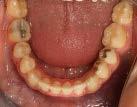

En las fotografías intraorales (Figura 3) observamos una clase II molar bilateral, clase II canina derecha, clase III canina izquierda, apiñamiento severo superior y moderado inferior, presencia de mordida abierta anterior y posterior a nivel de premolares (Figura 4), forma de arco triangular en la arcada superior y forma de arco oval en inferior, ausencia del OD 46 y presencia de un diente supernumerario.

Figura 4. Vista oclusal superior e inferior. Figura 5. Frente, perfil.

En las fotografías oclusales observamos la forma de arco oval, la solución del apiñamiento y el cierre de la mordida abierta. (Figura 8)

Extracción de primeros molares permanentes en la corrección de mordidas abiertas severas Figura 8. Oclusal superior e inferior. Figura 9. Sobreimposición.